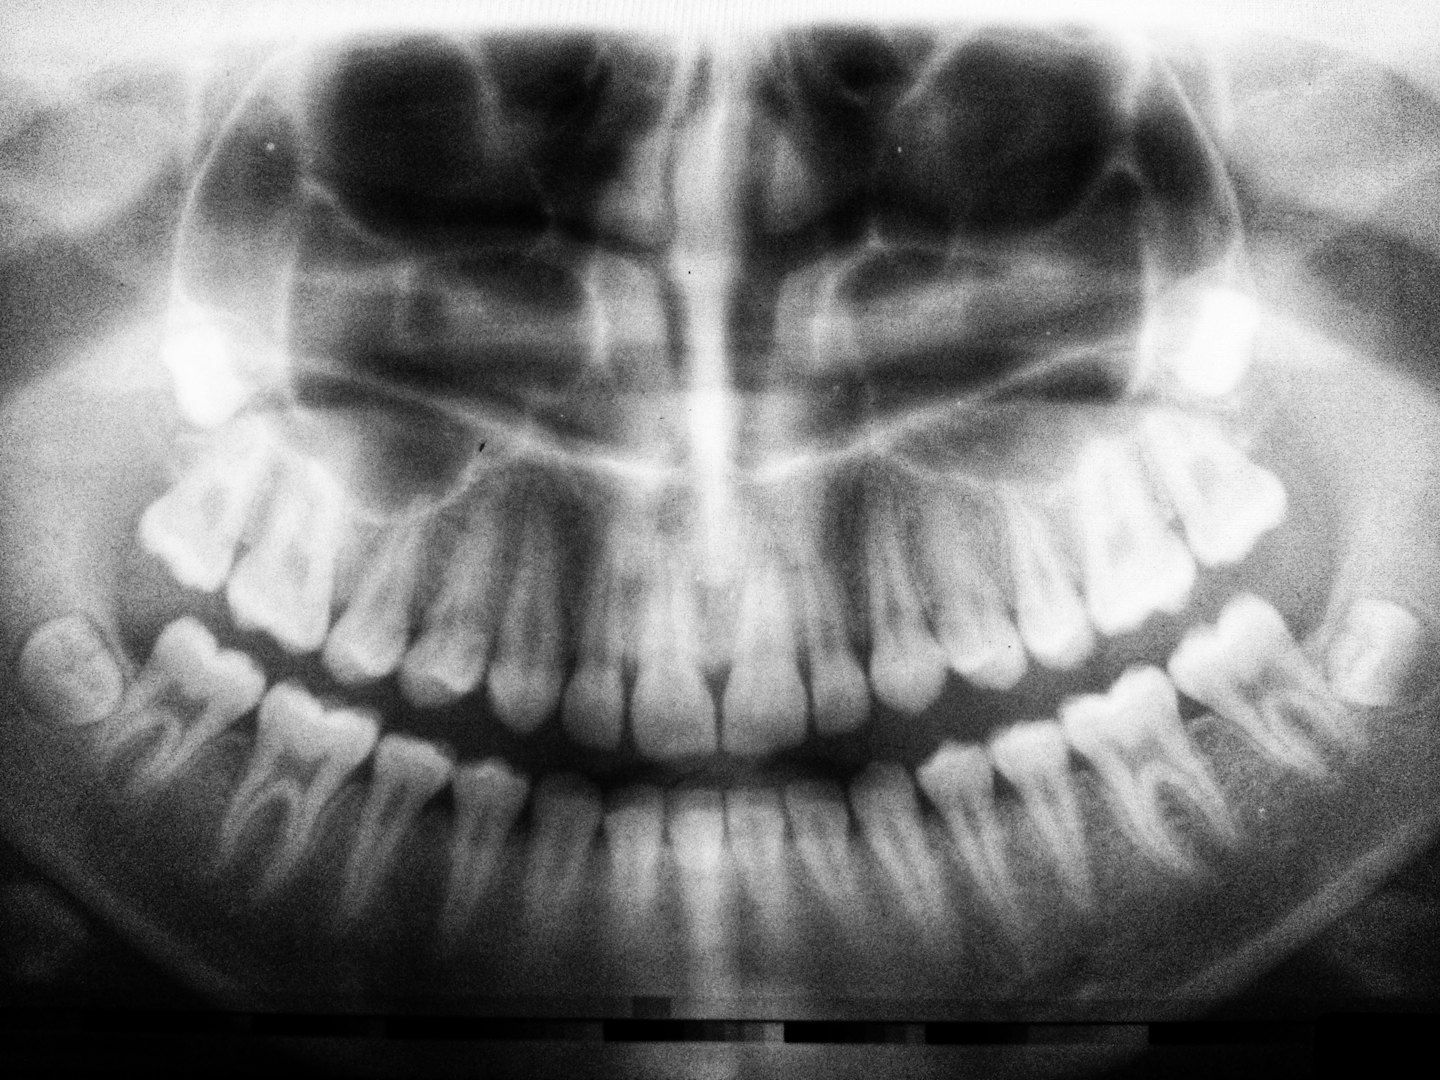

Professionell tandvård med fokus på din munhälsa

Leendehuset klinik erbjuder engagerad tandvård med målet att förbättra din munhälsa och skapa trygga leenden för livet.

Professionell tandvård i en trygg och harmonisk atmosfär